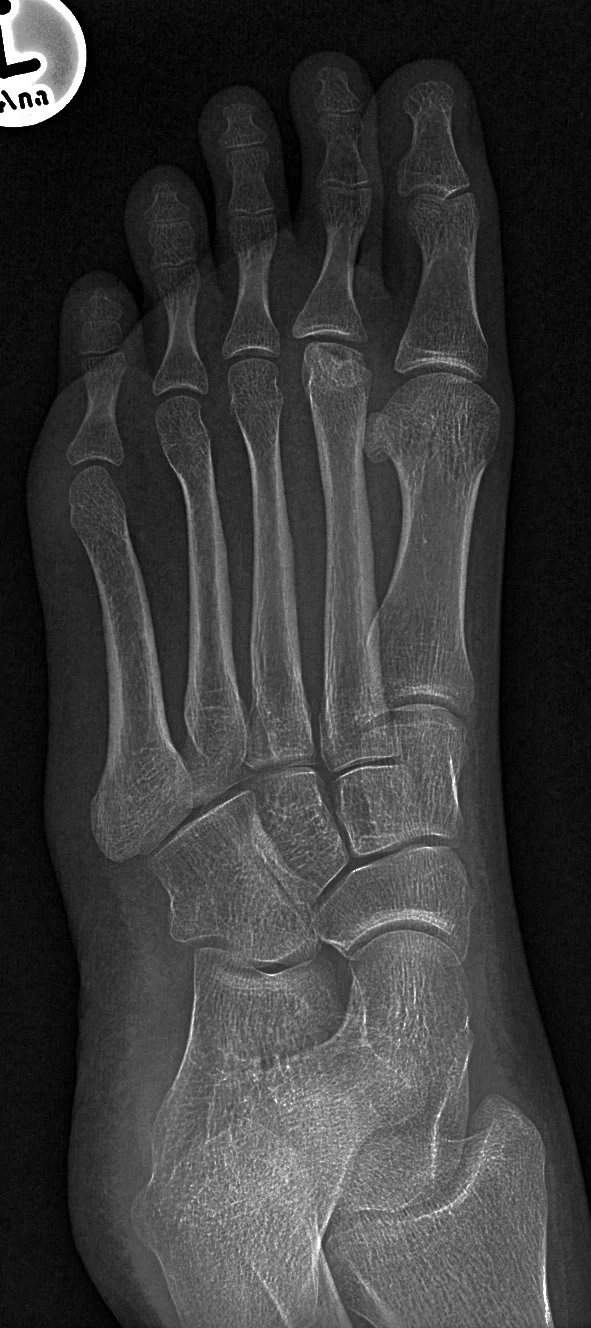

Lisfranc ligament

• Connects medial cuneiform to 2nd & 3rd metatarsals

• Acts as stabilizer of midfoot

• Injury:

• Forefoot abduction - plant and twist motion, foot caught in horse stirrup

• Forced plantar-flexion

• 3 Types of Radiographic injury:

• Homolateral - basically all digits move laterally (1st digit may remain in place) (2nd picture)

• Isolated - Has dorsal metatarsal dislocation

• Divergent - basically 1st digit moves medially and all other digits move laterally (increase space between 1st and second digits) (3rd picture)

• Fleck sign - Lisfranc injuries + fracture of base of 2nd metatarsal (most common associated fracture)